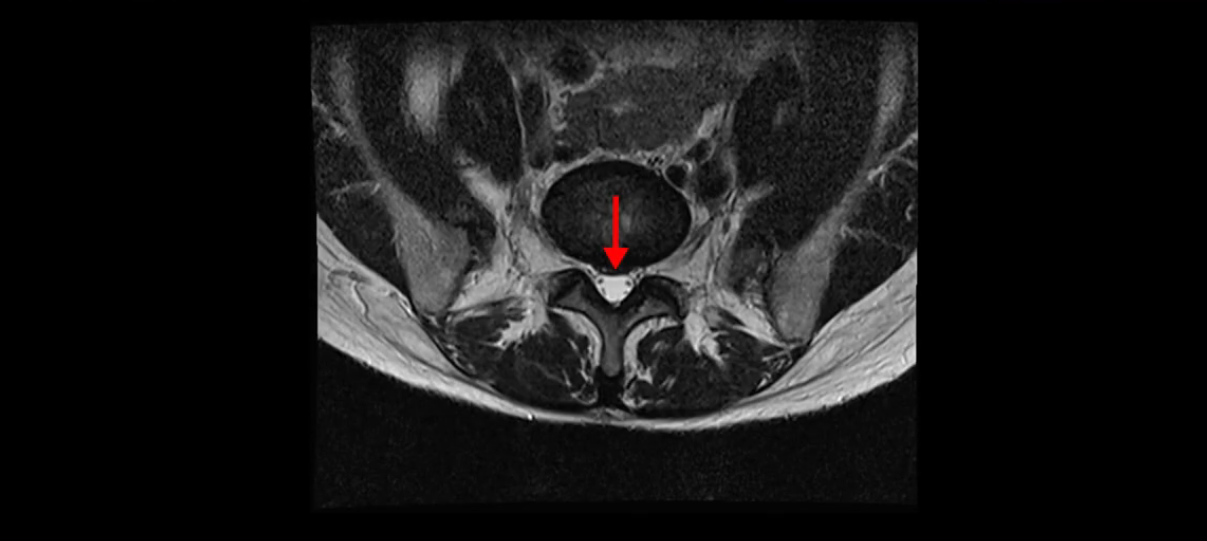

우선 이분의 MRI를 보고 먼저 설명을 드린 후 이런 환자분들의 통증의 원인은 무엇인지, 그리고 치료는 어떻게 해야 하는지 자세히 설명 드리겠습니다.

이분 MRI를 보시면 두 마디의 퇴행성디스크가 있습니다. 그리고 디스크가 조금씩 밀려 나와 있고요. 그런데 디스크 탈출 정도는 두 마디 다 심하지 않습니다. 4번 5번에는 디스크 탈출이 약간 있고,

척추관협착도 약간 진행이 되고 있고요.

5번 1번은 디스크 탈출이 가운데 쪽으로 살짝 있습니다.

또한 양쪽 신경 가지가 빠져나가는 추간공은 매우 넓은 상태입니다.

중요한 것은 이 정도 경미한 탈출과 협착으로는 양쪽 다리가 저리고 아플 수가 없습니다.

이분 MRI를 보시면 퇴행성디스크가 있고 약간의 협착이 있지만 이 정도의 퇴행성디스크와 협착으로는 신경이 눌려서 양쪽 다리가 저리고 아픈 증상이 나올 수가 없습니다. 그래서 MRI와 이 환자분의 다리 증상이 매치가 안 된다고 하는 의사들이 많은 겁니다.